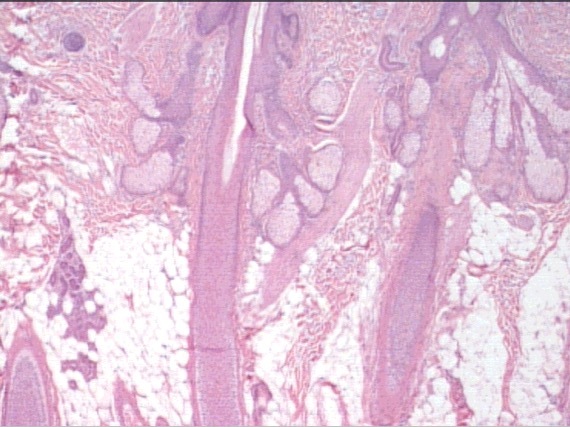

skin

hair follicle

subacous glands

arrector pili m. (sympathetic)

hypodermis (adipose)